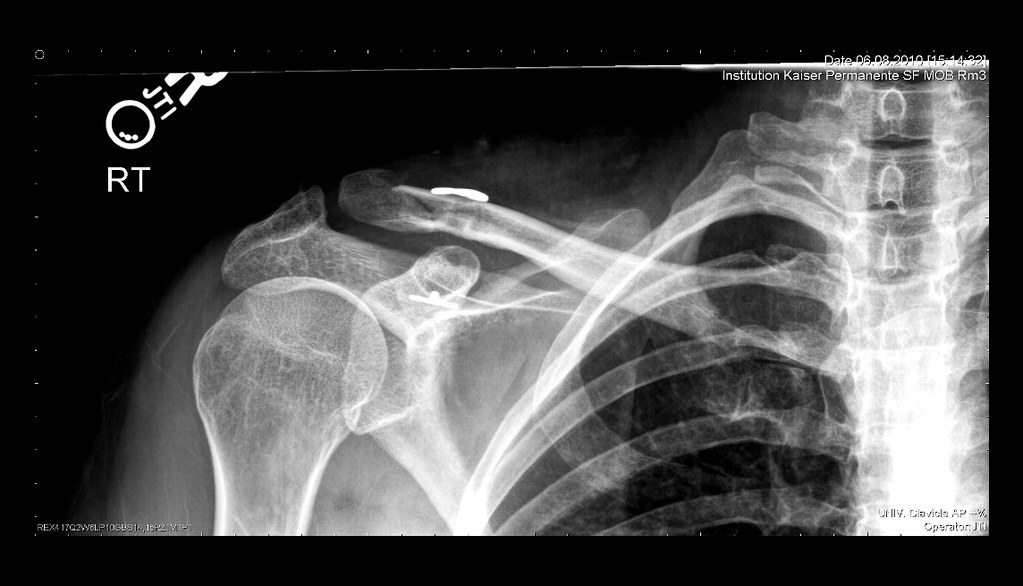

From www.flickr.com

Clavicle Post Surgery Xray After getting the staples out. … Flickr Staples In Shoulder Surgery As neither method was superior over the other in terms of patient satisfaction, adverse. In shoulder replacement surgery, the damaged parts of the shoulder are removed and replaced with artificial components, called a prosthesis. In this article, we detail the history of surgical staples and how the technology has evolved, contributing to the development of modern surgical techniques, as well. Staples In Shoulder Surgery.